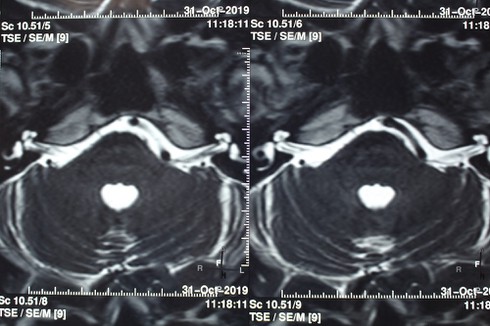

Hình ảnh dây thần sinh số VII bị chèn ép trên phim chụp. |

Nam bệnh nhân N.H.T (37 tuổi, ngụ ở Bình Dương) nhập viện với triệu chứng nửa mặt trái, mắt và miệng giật liên tục. Qua khai thác bệnh sử, khám bệnh và chụp MRI não phát hiện dây thần kinh số VII bên trái của bệnh nhân bị một mạch máu chèn ép. Bệnh nhân được chẩn đoán bị co giật nửa mặt trái.